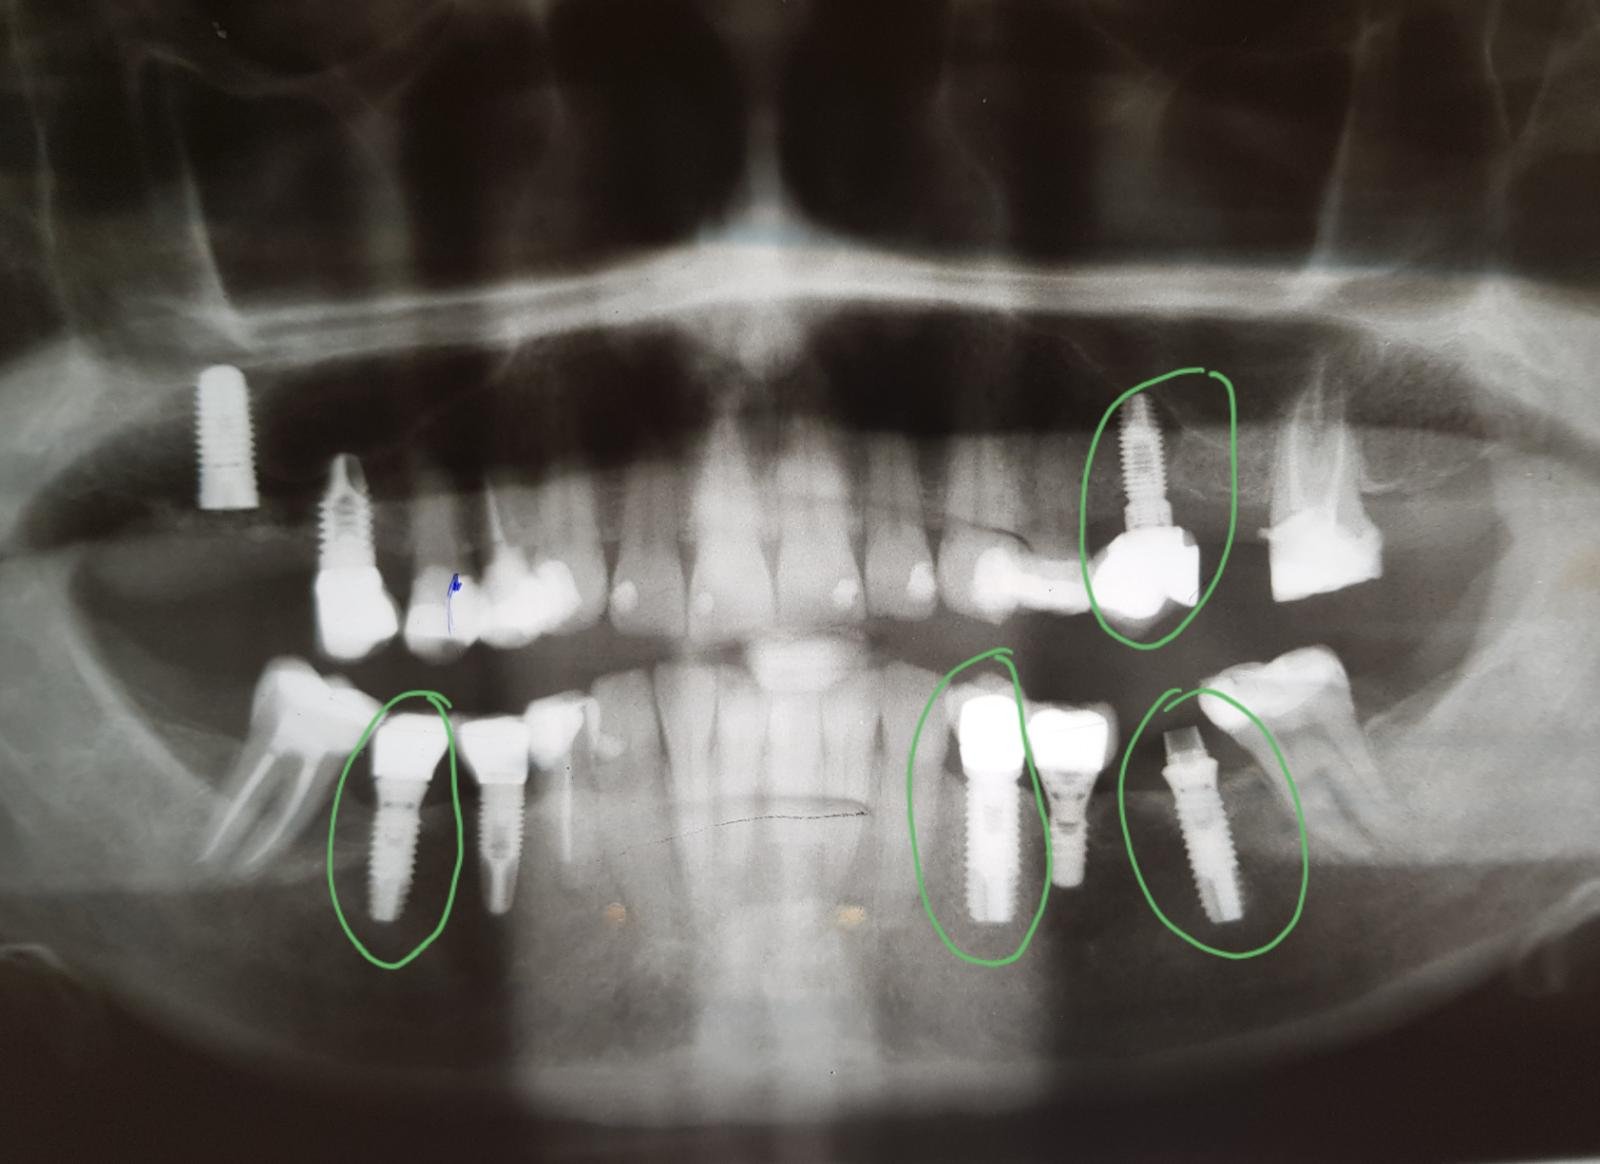

Necesito saber que implantes son estos colocados en 4 cuadrante por iDental en Granada. Gracias

Buenas tardes! Tengo una paciente que vino de idental y refiere que la corona del implante del 22 esta "floja". Efectivamente a la palpación se le mueve. Me gustaría saber [...]